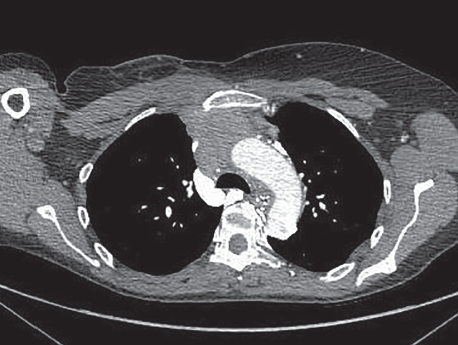

Figure 2. CT scan of the chest with intravenous contrast shows a superior mediastinal mass causing phrenic nerve palsy.

Radiographic images. Initial chest radiograph on admission (Figures 1a and 1b) showed new elevation of left side hemidiaphragm. Further evaluation of a CT scan of the chest with intravenous contrast revealed small bilateral pulmonary emboli along with a superior mediastinal mass (Figure 2). The patient underwent an anterior mediastinoscopy and biopsy confirmed it to be a metastatic adenocarcinoma from breast cancer. The elevation of diaphragm was probably due to the paralysis of the phrenic nerve caused by compression of the tumor mass.